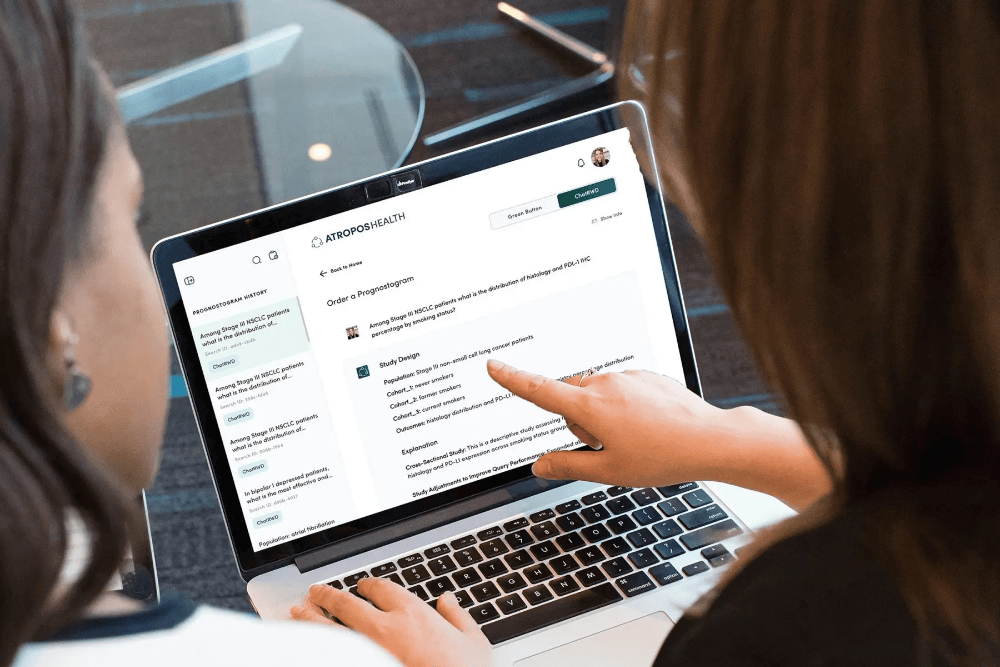

2、Atropos Health ChatRWD:临床数据实时查询系统

当通用人工智能在医疗建议领域尚存争议时,Atropos Health推出的ChatRWD为临床医生提供了不违背希波克拉底誓言的AI工具。该系统依托3亿条匿名患者数据库,允许医生在数秒内模拟定制化临床试验,据称其答案可靠率高达94%,远超通用AI模型不足10%的水平。

美国旧金山米尔斯半岛医疗中心的实践印证了其价值:当麻醉科医生对术前是否应停用糖尿病药物存在争议时,通过ChatRWD对1.3万名糖尿病患者进行分析,最终证实无需停药也不会增加手术风险,成功避免了不必要的用药中断和手术改期。